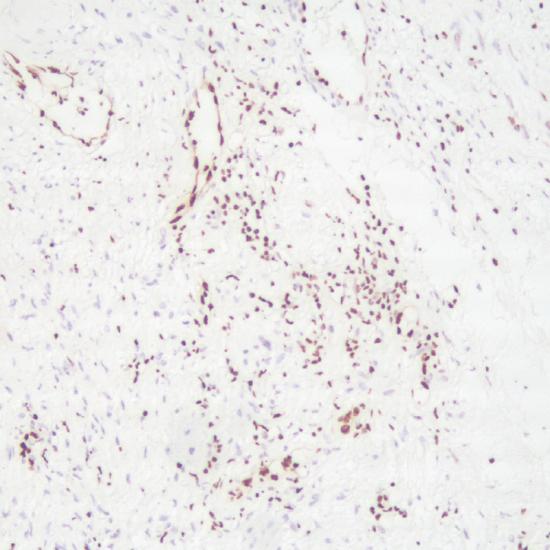

ERG抗體試劑(免疫組織化學(xué)法) 閩廈械備20190129號

• 陽性部位:

細胞核

• 陽性對照:

前列腺癌

ERG屬于EST-家族轉(zhuǎn)錄因子,約50%前列腺癌ERG陽性,提示TMPRSS2-ERG基因融合。TMPRSS2-ERG基因融合與前列腺癌的侵襲性和預(yù)后相關(guān)。了解TMPRSS2-ERG融合基因在前列腺癌中的作用機制至關(guān)重要,可以為前列腺癌的診療提供幫助。